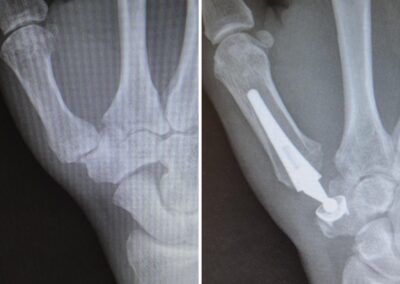

RIZARTROSIS (artrosis en la base del pulgar)

La rizartrosis es el cambio degenerativo de la articulación trapecio-metacarpiana (TMC), constituye una enfermedad muy habitual, especialmente en mujeres mayores de 50 años. Cerca del 30% de las mujeres posmenopáusicas presentan cambios degenerativos radiográficos en la articulación TMC, aunque algunas son asintomáticas . Menos frecuentemente esta enfermedad afecta a los hombres (menos del 10%).

Es una patología muy incapacitante, ya que produce dolor a la movilización del pulgar, disminución de la fuerza, perdida de destreza en la pinza, limitación de la movilidad y deformidad progresiva de la columna del pulgar por aducción del 1er dedo, subluxación radial de la base del 1er metacarpiano y la consiguiente hiperextensión de la articulación metacarpofalangica.

La clasificación de Eaton y Littler esta destinada a hacer una elección terapéutica racional entre los diferentes métodos en función de los estadios evolutivos radiológicos.

Las artroplastias TMC también se han empleado para esta patología. Existen numerosos modelos. El implante ideal debe permitir una reconstrucción articular anatómica, debe ser biocompatible, con un periodo de supervivencia largo, no cementado para evitar los problemas frecuentes de descementación o aflojamiento en la interfase cemento-hueso y no debería constituir la última solución terapéutica posible en caso de fracaso